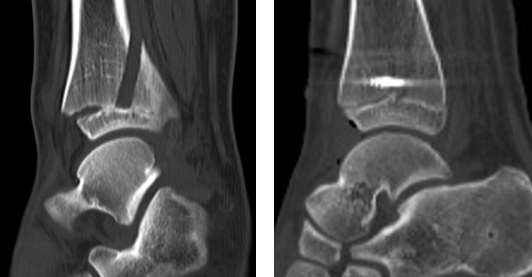

术前CT(左图)术后CT(右图)

第二天,业务院长石荣剑、曹广超主任、赵亮主治医师手术团队为患儿进行了“关节镜下左踝关节滑膜清理+胫骨骨折复位内固定术”,手术取2个切口,关节镜进入关节腔内,见关节内滑膜增生,部分呈絮样悬浮状,刨刀清理增生滑膜组织。探查见胫骨远端骨折累及前踝、内踝,骨骺分离,骨骺骨折,关节镜监视下,对骨骺予以保护,复位胫骨远端骨折端,螺钉固定断端。手术40分钟顺利结束。

赵亮医生先为患儿进行相关检查,发现其左胫骨远端骨质断裂,累及内踝、前踝,骨骺受累。骨骺是人体身高长高、骨骼发育的重要解剖部分,赵医生建议行关节镜下微创手术治疗,该术式创伤小,而且踝关节镜手术操作简便,仅需2个0.5cm切口,手术时间短,术中出血少,术后2-3天患儿即可出院,回到课堂,手术的费用相对较低,对其家庭负担较小。